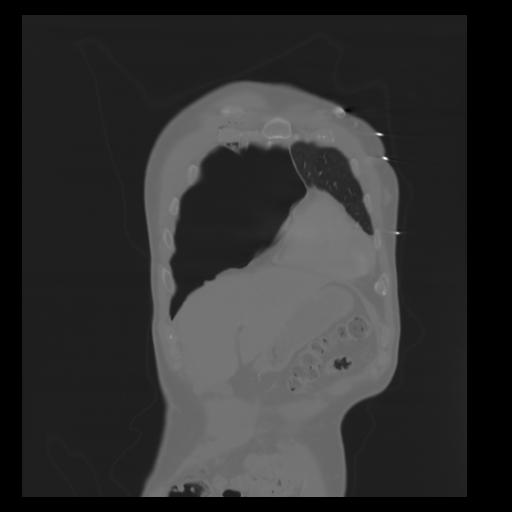

29 CUERPO,CE,Coronal,3.000,CUERPO,Coronal,